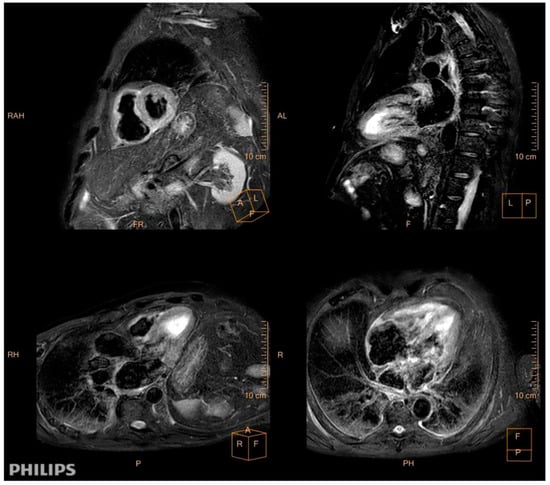

A 78-year-old man with a previous history of hypertension presented with progressive dyspnea, unexpected weight loss, Raynaud phenomenon, muscle weakness, dysphony, dysgeusia, and right hemifacial hypoesthesia, which had persisted for 3 months. A physical examination revealed bi-basal fine crackles and bilateral proximal muscle weakness in the upper and lower extremities. A dermatological examination revealed no cutaneous abnormalities. An electrocardiogram showed low voltages, sinus rhythm, first degree atrioventricular block, and QS-wave morphology in the anterior precordial leads. Bilateral interstitial infiltrates were found in the chest X-ray, and biochemical tests showed elevations in C-reactive protein (76 mg/L) and skeletal muscle and cardiac enzymes (creatine kinase: 1942 U/L, creatine kinase–muscle/brain: 50 ng/mL, and hs-troponin I: 31,125 pg/mL). The patient was admitted. An electromyogram showed signs of chronic radiculopathy L4–L5–S1 without acute axonal damage and primary affectation of muscular fiber in inferior extremities (fibrillation and positive waves in right psoas). During voluntary contraction, we observed many small polyphase complexes with an early recruitment pattern. The vastus lateralis and medial right gastrocnemius showed a big polyphasic complex with a reduced pattern without spontaneous activity. The deltoid and right biceps muscles had an interferential pattern without spontaneous activity. Capillaroscopy showed a reduced number of capillaries and avascular areas, and central nervous system magnetic resonance imaging (MRI) results were unremarkable. Thoracoabdominal computed tomography (CT) revealed nonspecific interstitial pneumonia and whole-body positron-emission tomography/CT revealed diffuse myocardial uptake. A cardiac MRI revealed mild systolic biventricular dysfunction, inferoseptal hypokinesia, biatrial dilatation, diffuse edema, and fibrosis in the atrial walls and right ventricle. These features fulfilled the Lake Louise criteria for myocarditis (Figure 1).

Figure 1. Cardiac magnetic resonance imaging (MRI). Diffuse myocardial edema in T2-weighted edema images (SA, short axis; LA, long axis; 3C, three chamber; 4C, four chamber).